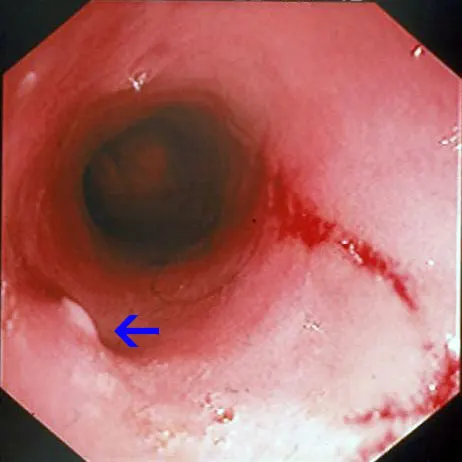

Endoscopic appearance of the normal proximal duodenum in a dog. A lymphoid aggregate (A, arrow) is clearly visible along the lateral mucosal wall. This structure should not be biopsied as such samples confound histologic determination of lymphocytic enteritis. The major duodenal papilla (B, arrow) and a linear mucosal erosion caused by passage of the endoscope through the cranial duodenal flexure are shown in B.

Retrograde ileoscopy should be performed as part of routine lower GI endoscopic examination in large dogs; it is contraindicated in small dogs and cats because it may cause too much trauma. This procedure is useful when an insufficient quantity or poor-quality duodenal biopsy samples have been obtained. It necessitates thorough colonic cleansing and advancement of the endoscope tip through the ileocecal sphincter in dogs (A).

Note the prominent and protuberant ileocolic valve (arrow); focal areas of hemorrhage are due to a previous mucosal biopsy. Also note that the ileal mucosa has an identical appearance to that of the proximal duodenum (B).